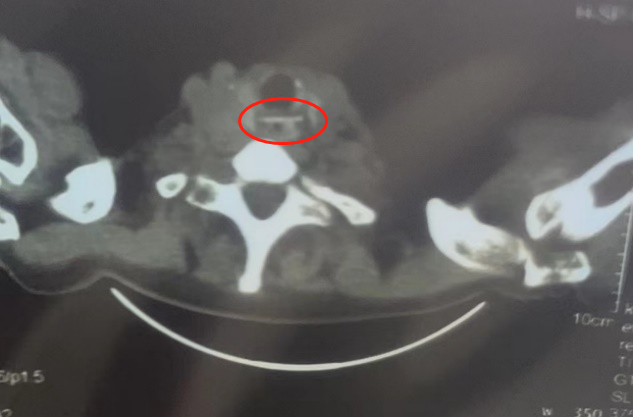

CT上嵌入食管的鸡骨

医务处、感控处多方联动,立即将患者闭环转诊至我院发热门诊。经仔细询问病史,5小时前,老人家不慎吞食鸡骨。在随后的CT检查中,发现一根长约2cm的鸡骨头横跨在食管颈部,一端刺入食管壁,给造成患者极大的痛苦。病情紧急,时间较久,一旦刺穿,会造成感染,严重时危及生命。